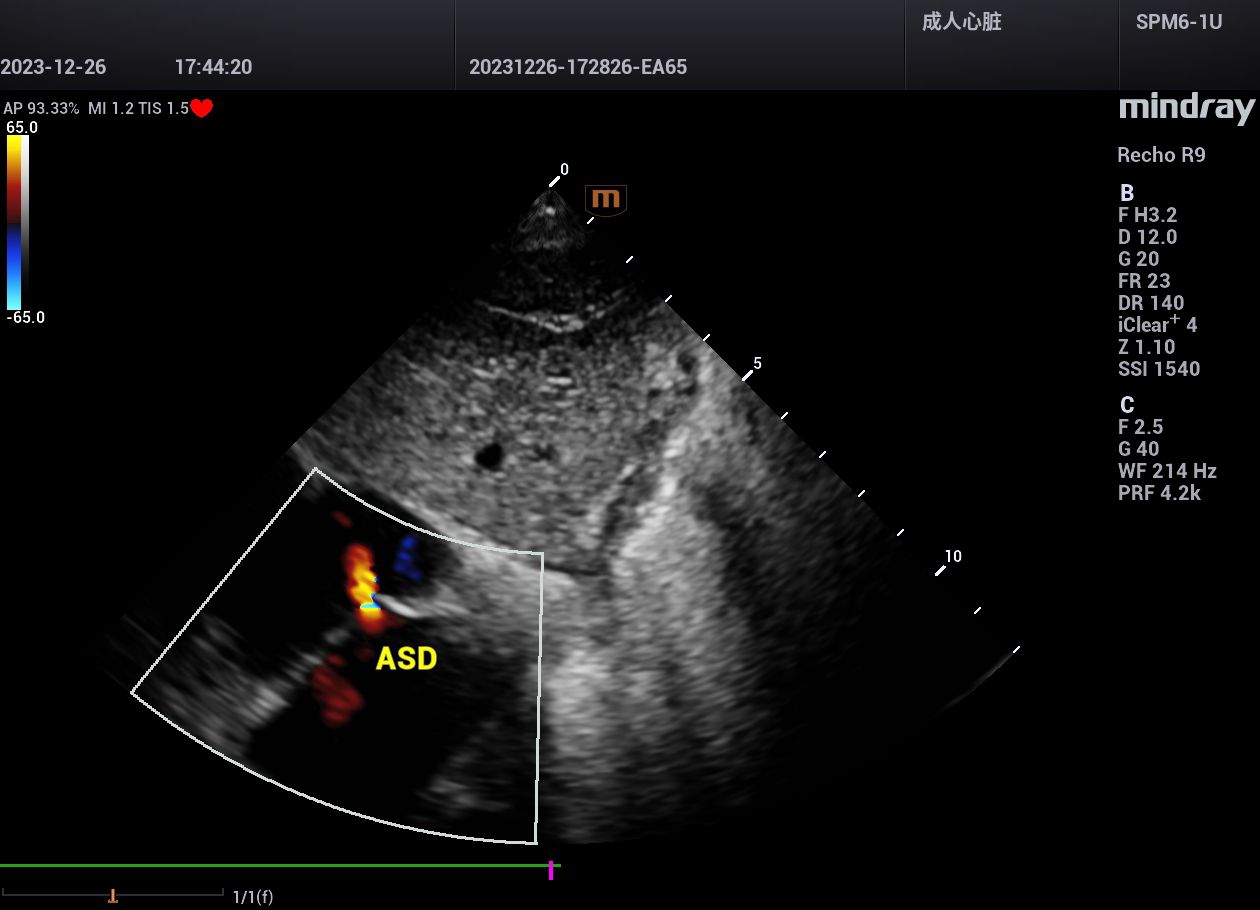

病例,房间隔缺损(ASD),广西中医药大学第一附属医院,2024年在广西

迈瑞鲲鹏Recho R9,助力实现超声事业高质量发展